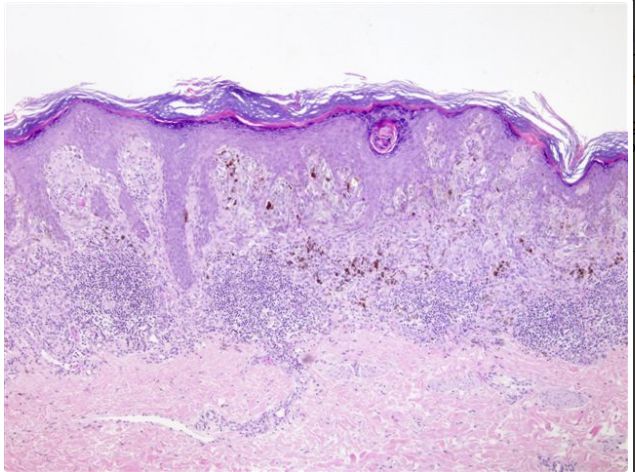

Cutaneous Lymphomas